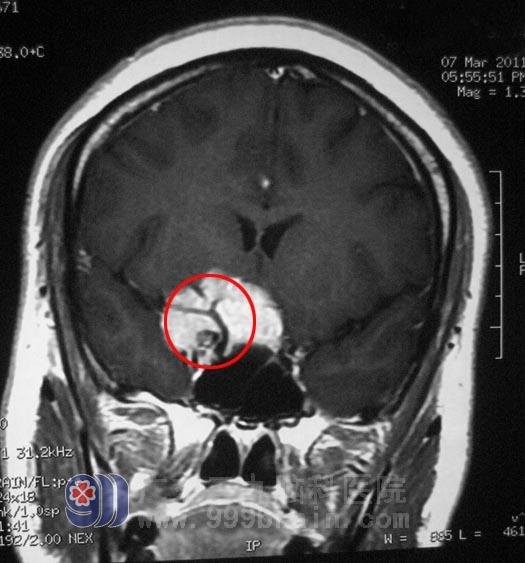

神经外五科鲁明主任分析后指出:许女士右眼视力下降与右侧鞍区占位有关,从头颅MRI上看,右侧鞍区占位内有许多血管通过,右侧颈内动脉被肿瘤包裹,有受压变细,术中分离肿瘤可能损伤颈内动脉。经过慎重考虑决定先行造影栓塞后再行手术治疗,避免术中大量出血,减少手术的风险性。3月20日,许女士在介入室行肿瘤部分供血血管栓塞术。3月22日,由鲁明主任主刀,在全麻下行“右侧蝶骨嵴脑膜瘤切除术”, 术中见肿瘤位于右侧中颅窝底,其基底部位于右侧蝶骨嵴、前床突位置,包绕右侧颈内动脉并延伸至对侧鞍旁,右侧视神经被肿瘤包绕并向上抬起,右侧动眼神经、外展神经被肿瘤压迫位于肿瘤外侧,肿瘤质地较软,血供丰富。显微镜下小心分离,将肿瘤分块全切,椎动脉及其分支位于肿瘤后下方,过程中右侧颈内动脉及其分支、椎动脉及其分支、双侧视神经、外展神经及动眼神经保护完好,手术成功完成。术后患者病理结果为:(右侧蝶骨嵴)脑膜皮细胞型脑膜瘤,WHOI级。

▲手术前影像(红圈内为穿过肿瘤的动脉血管)